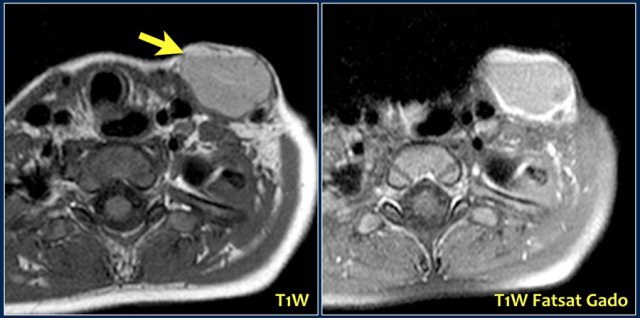

A 3-year-old boy presented suddenly with a supraclavicular mass.

Ultrasound showed a lesion with echogenic debris.

A hemorrhage in a preexisting lymphangioma was suspected.

Continue with the MRI.

The T1-weighted image shows a slightly hyperintense lesion with a fluid-fluid level (arrow).

After gadolineum administration there is enhancement of the cyst wall.

The lesion subsided with conservative therapy.